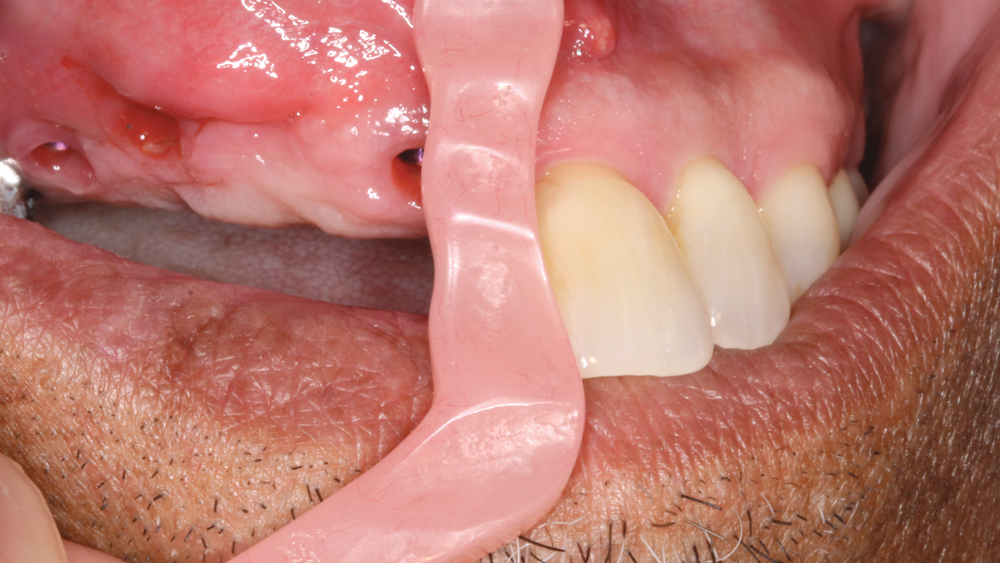

RESTORING THE CASE

Following integration of the implants for approximately four months, a final impression was made using Hahn Open-Tray Impression Copings (Glidewell Direct). The laboratory created a master cast and fabricated Inclusive® Titanium Custom Abutments for a cementable, implant-supported prosthesis. A screw-retained prosthesis was considered for this case, but because of the angulation of the seated implant fixtures, access holes would have exited through the facial aspect of the final prosthesis. Note that the patient is able to maintain the health of the tissue in the area of the restoration with a water pick, and the BruxZir Solid Zirconia material resists bacterial adhesion.